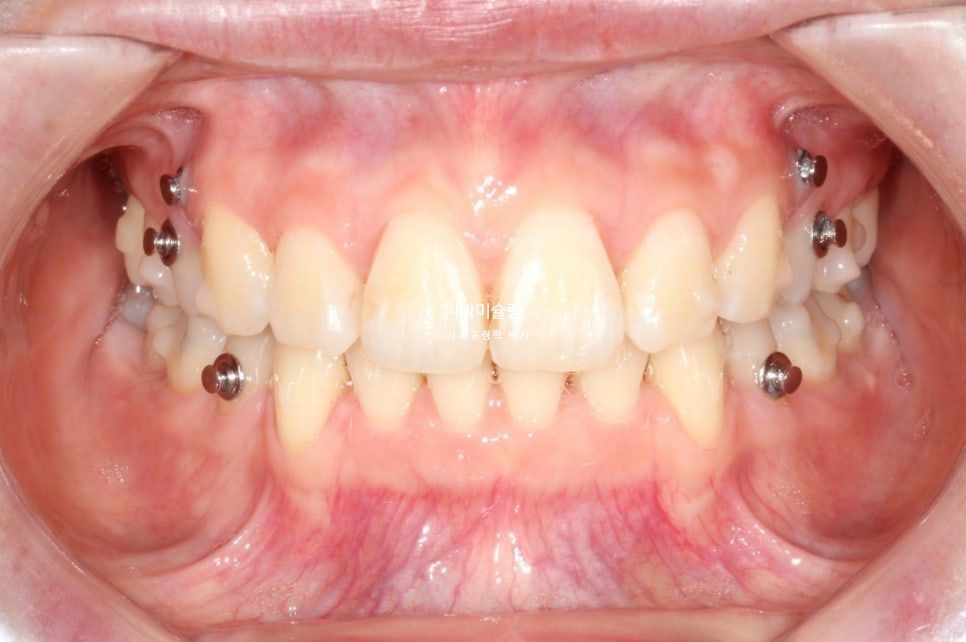

어쨎든 두번째 세트에서는 앞니 교합이 깊어짐을 방지하고 어금니 쓰러짐을 방지하고자 교정용 나사를 심고 뺏다꼈다 하는 고무줄 처방도 나갔습니다.

무난하게 70개 장치를 모두 낀 후 모습입니다.

약간의 과개교합이 남아있습니다. 중심선 개선이 더 필요힙니다.

어금니 교합은 좋습니다.